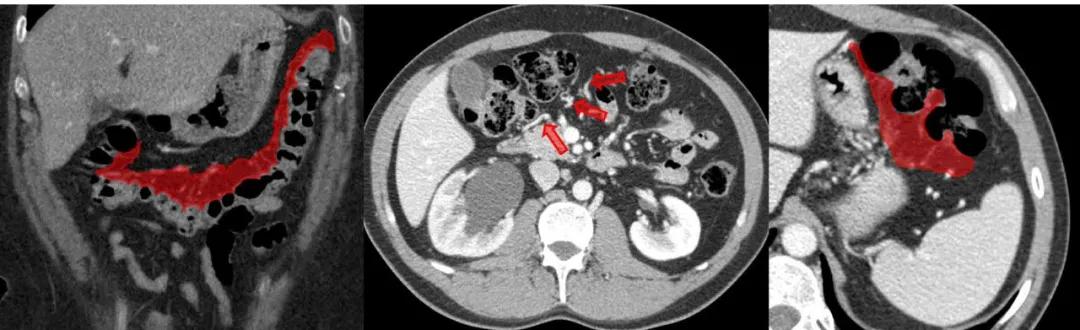

肠系膜根(橙色)。小肠系膜在肠系膜上动脉(SMA,红色箭头)的起始处有一个「肠系膜根」:小肠系膜从根区扇出,SMA 将其悬挂在后腹壁至回肠末端。

含肠系膜上动脉分支的小肠系膜(紫色)。

横结肠系膜(红色)和横结肠动脉(箭头)。